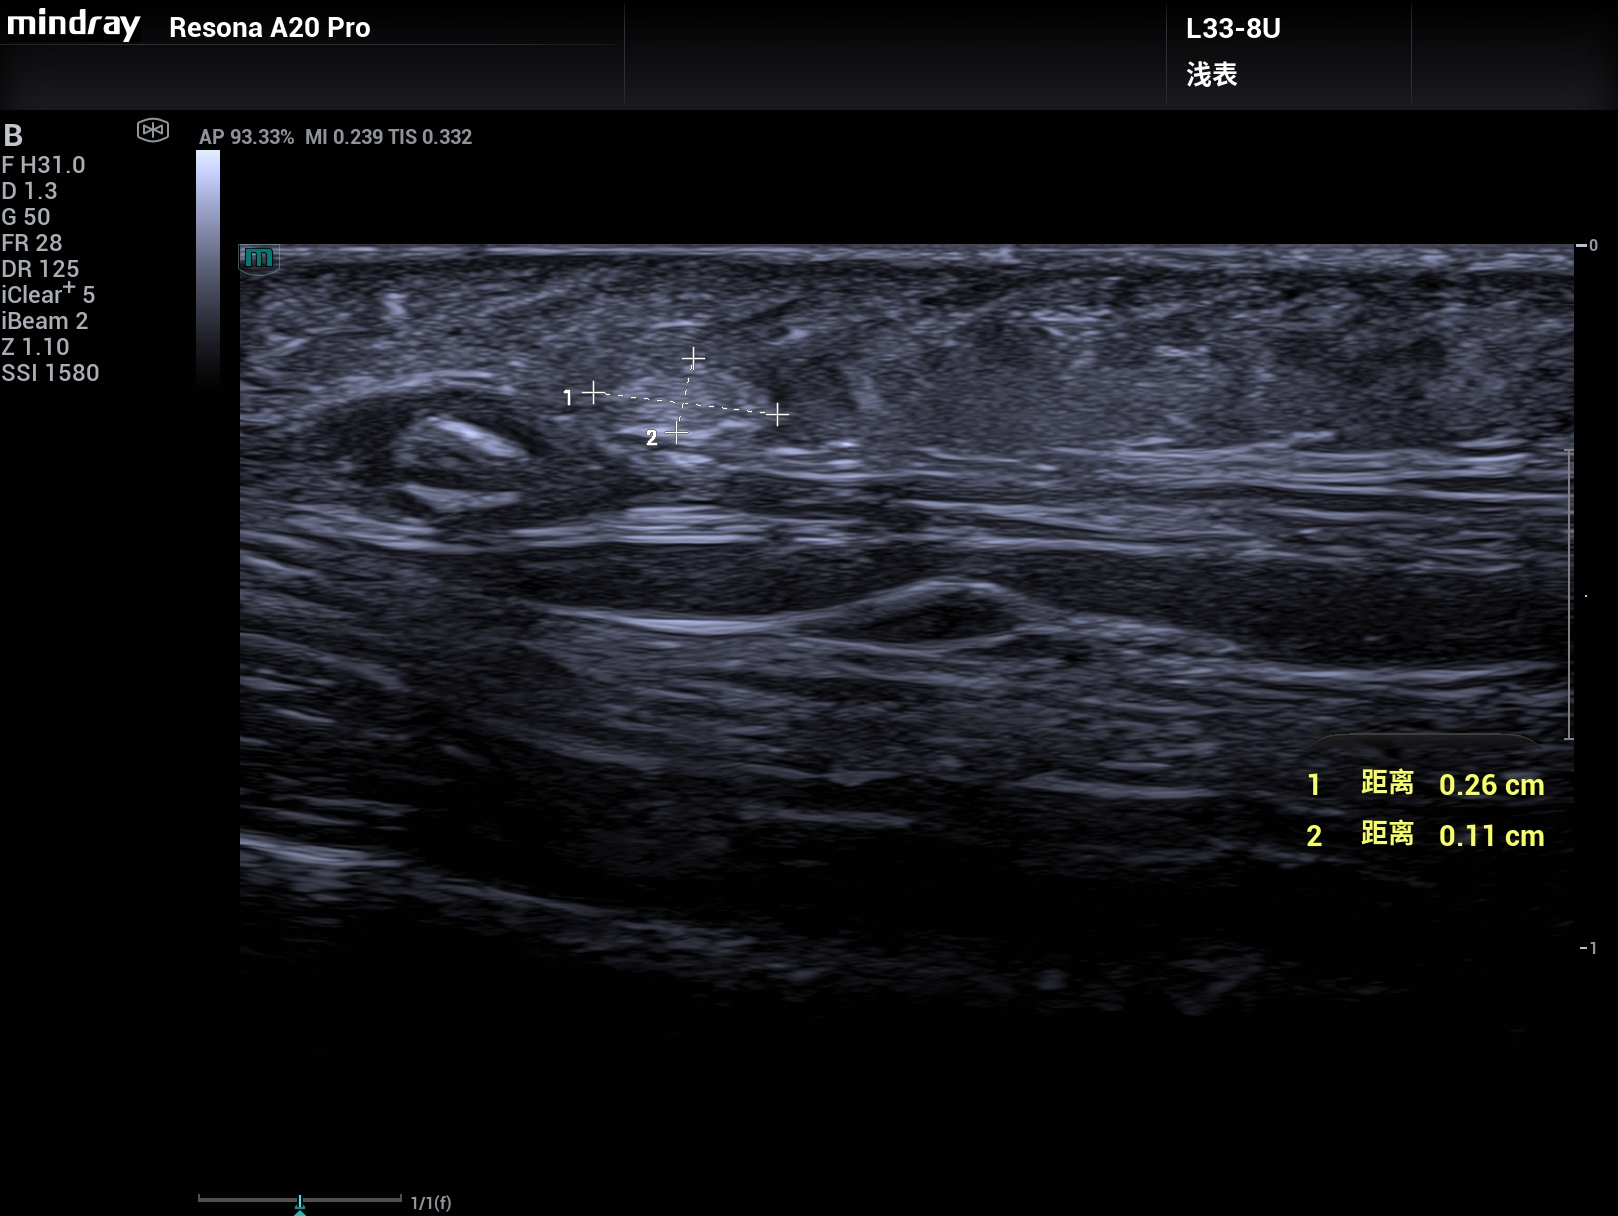

病例,33M和超微血流,头皮下1.5mm的2.6mm×1.1mm的脂肪瘤清楚显示,迈瑞Resona A20,2025年11月

常规高频探头是非常难检测显示出来!